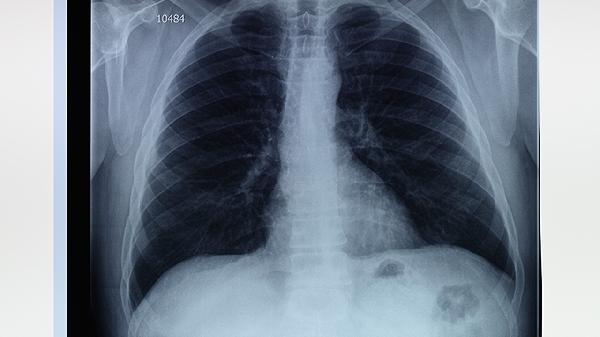

直径>5cm的肺大疱或反复气胸者需行胸腔镜肺大疱切除术,严重弥漫性肺气肿可考虑肺减容术。术后需配合胸廓振动排痰和渐进式运动康复。